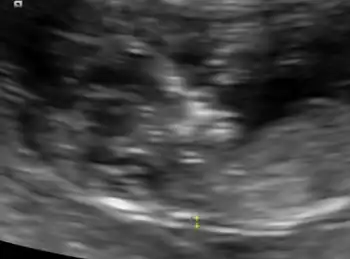

| An ultrasound showing a fetus with hydrops fetalis | |

Hydrops fetalis can be diagnosed and monitored by ultrasound scans.[1] An official diagnosis is made by identifying excess serous fluid in at least one space (ascites, pleural effusion, of pericardial effusion) accompanied by skin edema (greater than 5 mm thick). A diagnosis can also be made by identifying excess serous fluid in two potential spaces without accompanying edema. Prenatal ultrasound scanning enables early recognition of hydrops fetalis and has been enhanced with the introduction of MCA Doppler.[6]